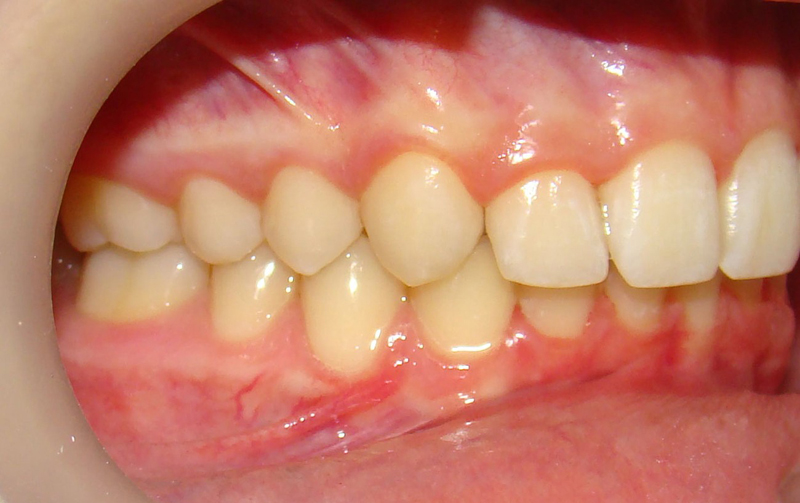

Девушке 14 лет. Получилось все исправить без удаления зубов

А это уже молодой человек 10 лет. Тоже получилось справиться без удаления. Хоть оно и было показано. Но мальчик очень упорно носил специальные аппаратики и резиночки. Покажу со всех сторон. Этот случай победил в конкурсе на конференции